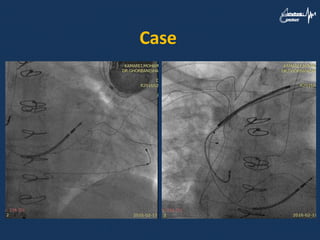

Case • A 73yr man was a case of ischemic cardiomyopathy with VT and LBBB • CRT-D was done successfully and there was improvement his heart failure • There was LV lead dislocation after two yeras

• 62.

• 63.

• 64.

• 65.